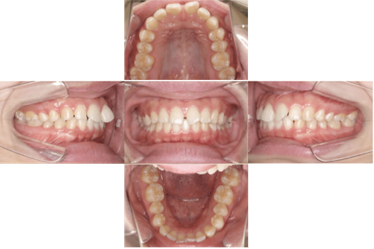

症例 ①

●マウスピース 部分矯正 ●23歳 ●治療期間:6ヶ月 ●費用:40万円

- 治療前 -

- 治療後 -

▶︎マウスピースを用いて、前歯の隙間・捻れの治療を行いました。